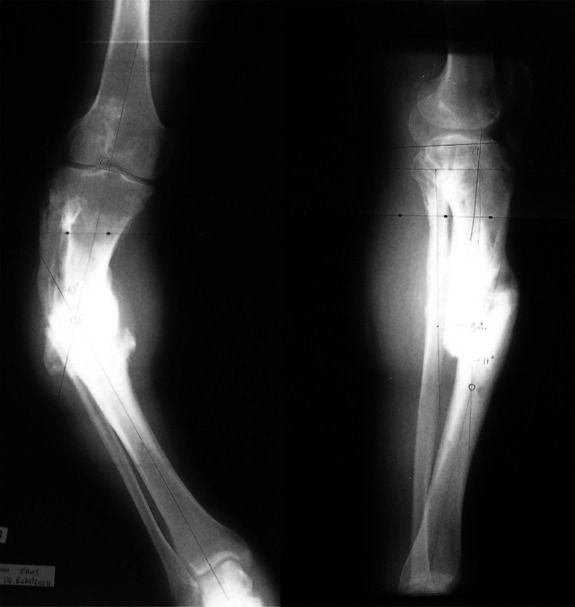

Abstract Image